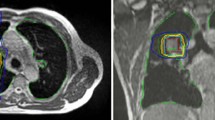

For the adrenal gland tumor, the PTV of the ITV-based plan overlapped in parts with the stomach, which resulted in a decreased dose coverage of the PTV compared with the MR-Linac plan, in order to meet the stomach dose constraint (see Table 4; Fig. 7). Hence, only 89% of the PTV was encompassed by the 50-Gy isodose. Although all other dose constraints were met in both plans, the dose to the spinal cord was substantially lower in the MR-Linac plan.

Treatment plan for patient 3 (adrenal gland metastasis) as applied at the magnetic resonance(MR)-Linac using gated treatment in breath-hold (a–c: axial, sagittal and coronal images). Retrospectively generated computed tomography-based plan with internal target volume (ITV) showing a larger treatment volume compared with the MR-Linac plan (d–f: axial, sagittal and coronal images). In this case, the ITV extends into the right lung in order to geometrically cover the entire area of tumor location during breathing motion